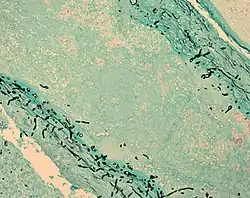

![]() Fungal cells (black lines) in infected brain tissue (cyan) | |